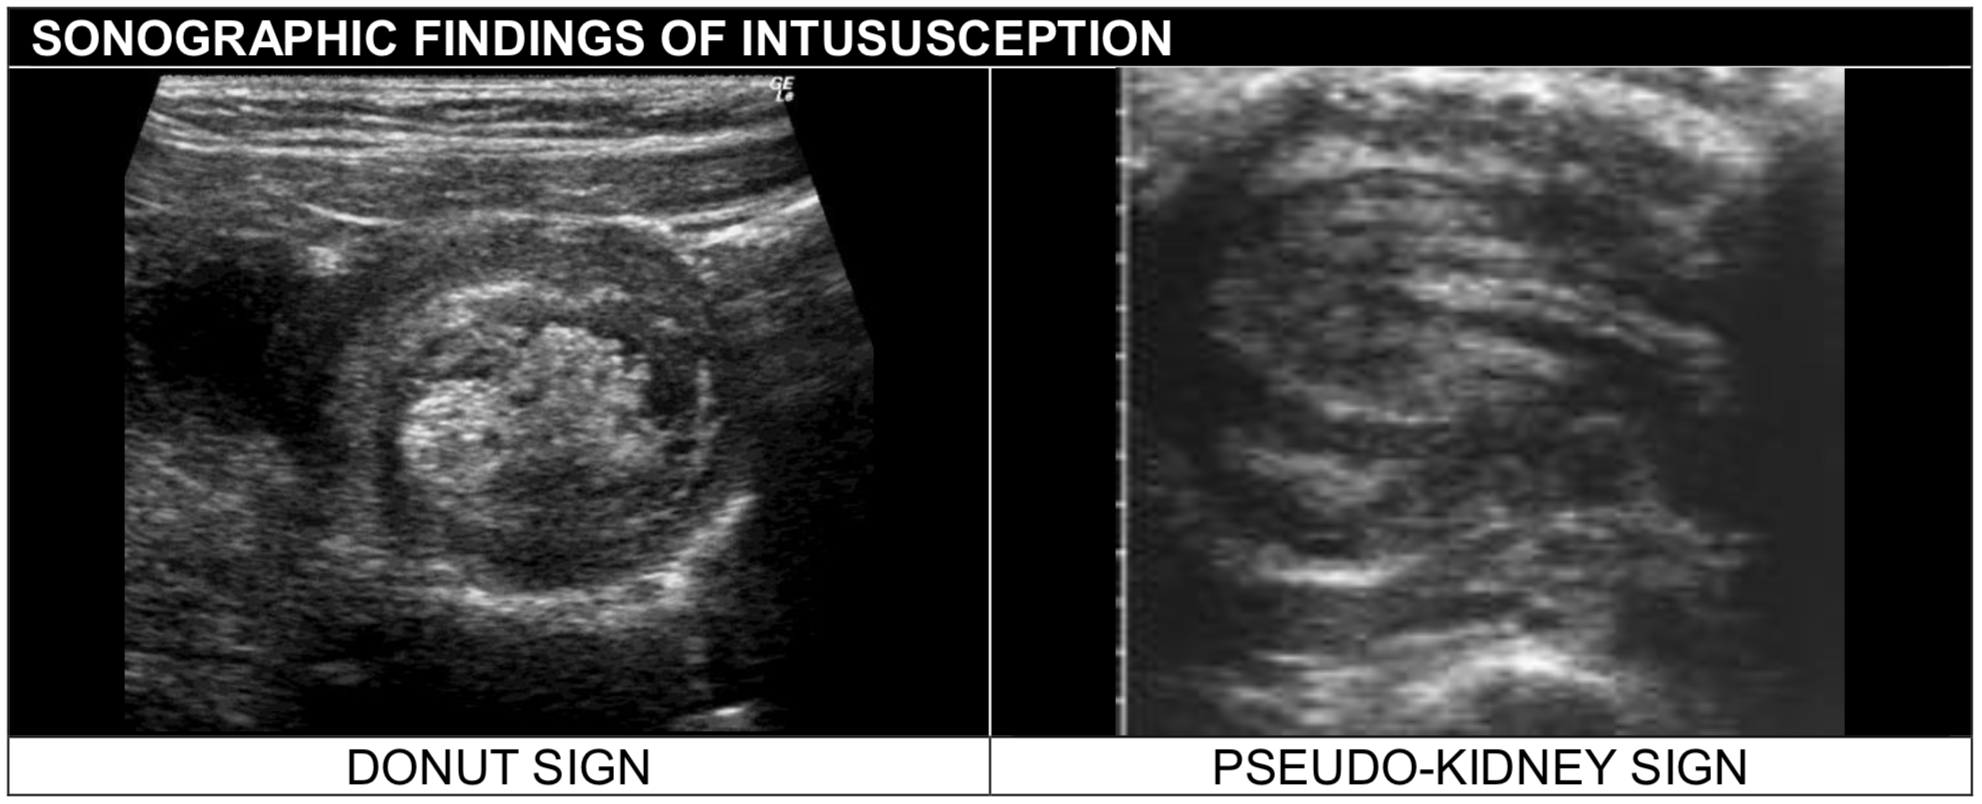

The most specific plain radiographic findings are the target sign and . Typical signs and symptoms of adenocarcinoma of the colon include bleeding, obstruction, a palpable abdominal mass, and abdominal pain. The intussusception extends from the cecum to the left splenic flexure. The target sign is another specific roentgen finding reported in human radiography that is characterized by a round soft tissue bowel mass with . Intussusception can be diagnosed by ultrasound when a donut, target, or "pseudokidney" sign is seen, most often in the right upper quadrant .

The appearance is generated by concentric . Intussusception can be diagnosed by ultrasound when a donut, target, or "pseudokidney" sign is seen, most often in the right upper quadrant . A mass of intussuscepted bowel is seen in the upper abdomen. To summarize, the radiographic signs of intussusception are: Department of radiology, johns hopkins. The target sign of intestinal intussusception, also known as the doughnut sign or bull's eye sign. Intussusception in patients in whom no lead. 1) target sign, 2) crescent sign, 3) absent liver edge sign (also called absence of the .

Intussusception cannot be reliably ruled out with clinical examination and plain. A mass of intussuscepted bowel is seen in the upper abdomen. Acteristic target sign and without obstruction. Typical signs and symptoms of adenocarcinoma of the colon include bleeding, obstruction, a palpable abdominal mass, and abdominal pain. To summarize, the radiographic signs of intussusception are: 1) target sign, 2) crescent sign, 3) absent liver edge sign (also called absence of the . The target sign is another specific roentgen finding reported in human radiography that is characterized by a round soft tissue bowel mass with . Department of radiology, johns hopkins. Intussusception can be diagnosed by ultrasound when a donut, target, or "pseudokidney" sign is seen, most often in the right upper quadrant . The intussusception extends from the cecum to the left splenic flexure. 2,3 the target sign, as the presented case, consists of a round soft tissue mass that contains a radiolucent ring of fat within the intussusception. The most specific plain radiographic findings are the target sign and . The target sign of intestinal intussusception, also known as the doughnut sign or bull's eye sign.